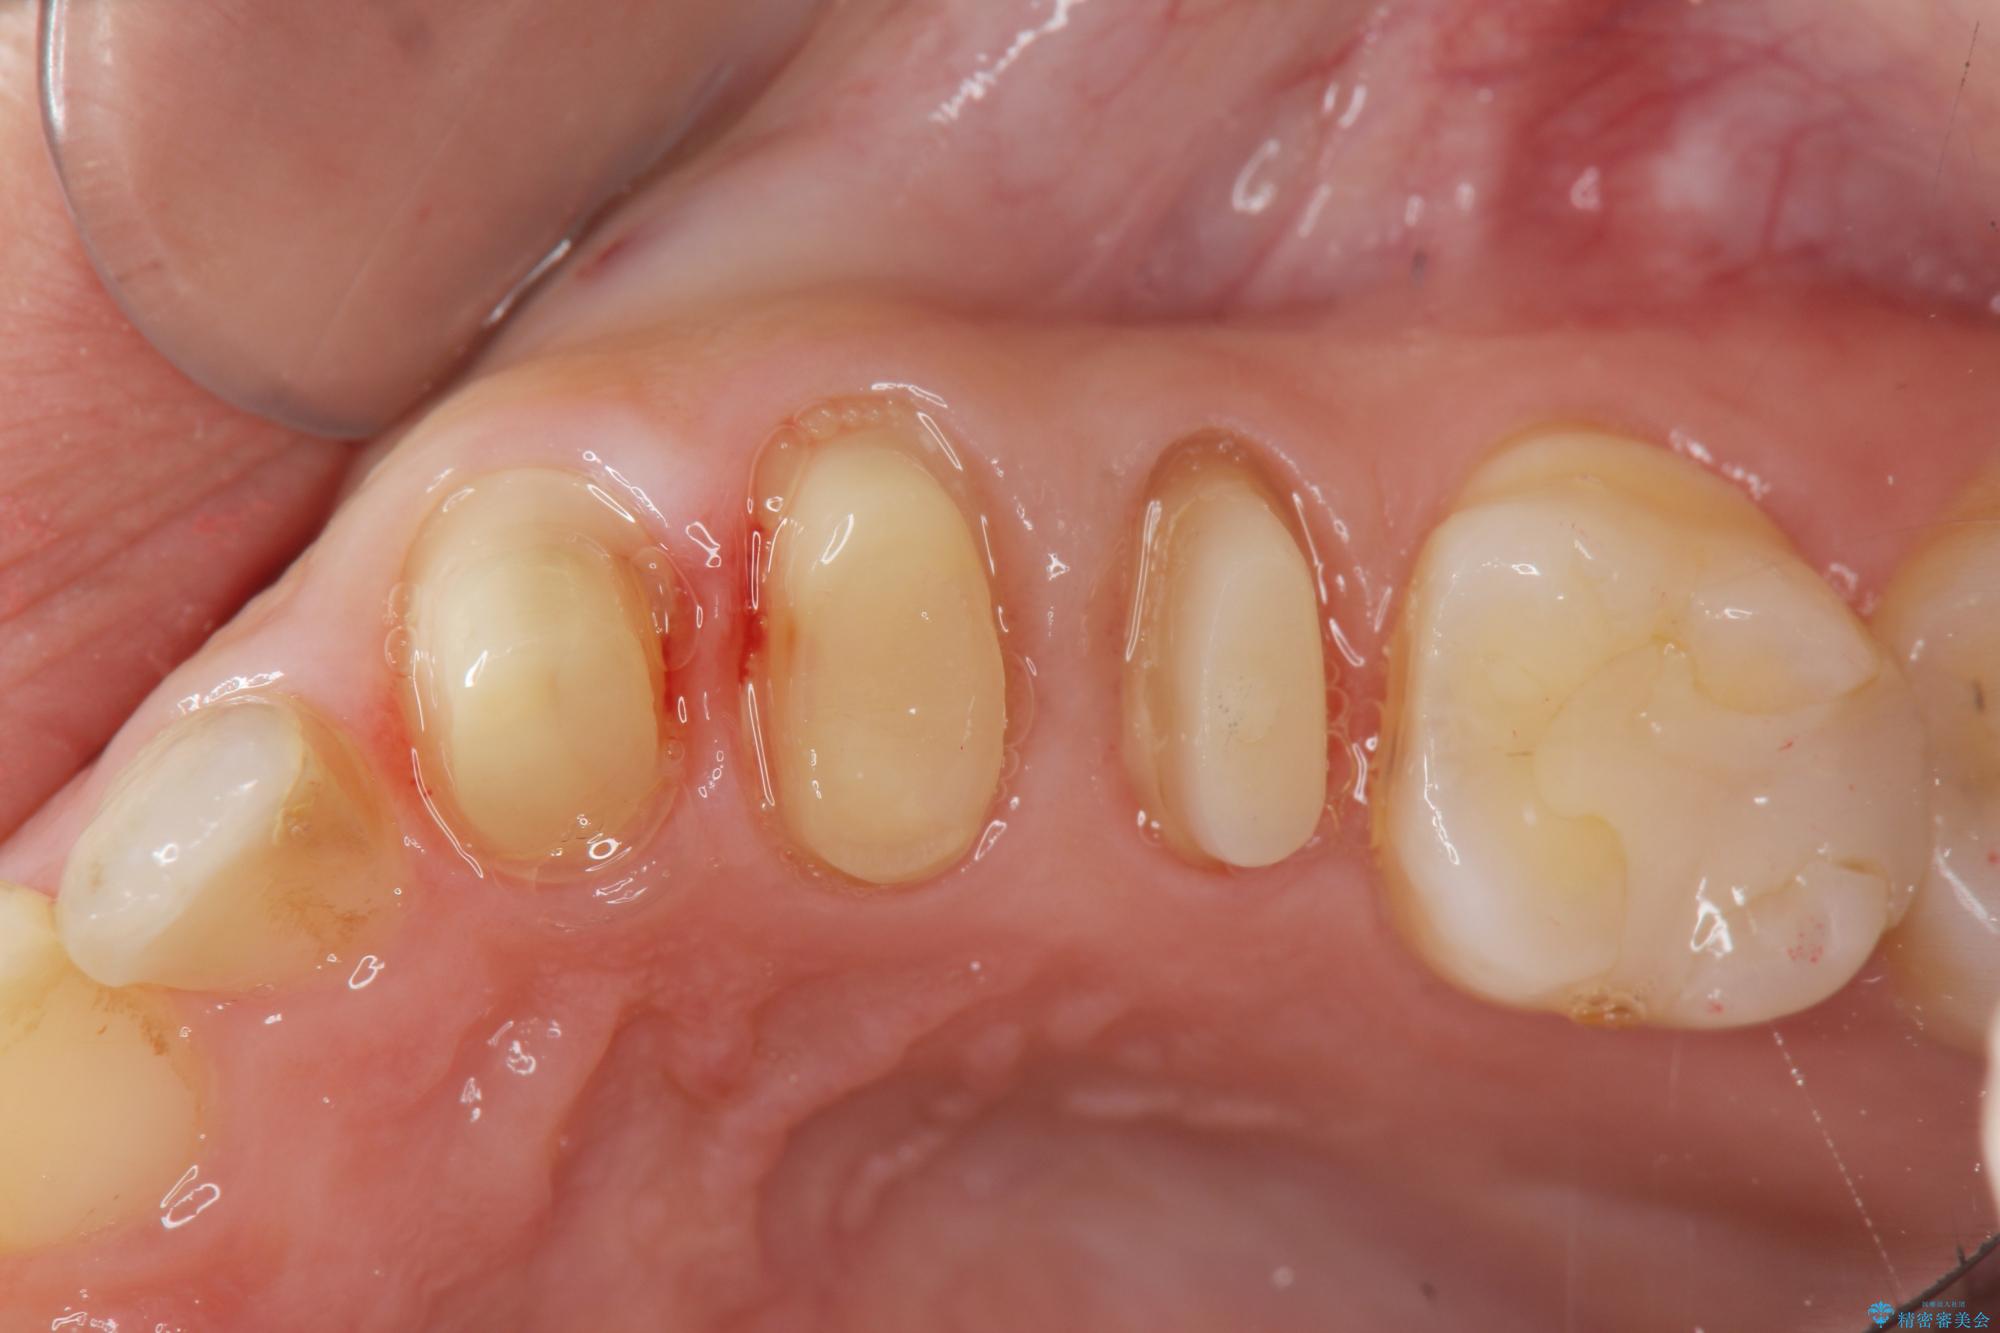

- 歯ぐきの腫れや、歯の内部が黒く見えることからの虫歯の治療を求めて来院されました。

虫歯が大きかったことから、神経の温存はできたものの歯ぐきよりも深い虫歯の問題を解決するため部分矯正治療を併用したセラミック治療を行うこととしました。

当初、歯ぐきよりも深い虫歯のぞんざいや、歯のポジションに問題がありましたがマルチブラケットを用いた部分矯正を行うことで適切な位置へと歯を移動させ、歯周環境を整えたセラミック治療を行うことができました。